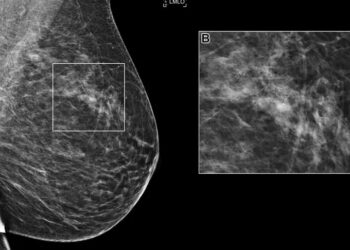

An international competition hosted by the Radiological Society of North America (RSNA) has demonstrated that AI models can independently interpret...